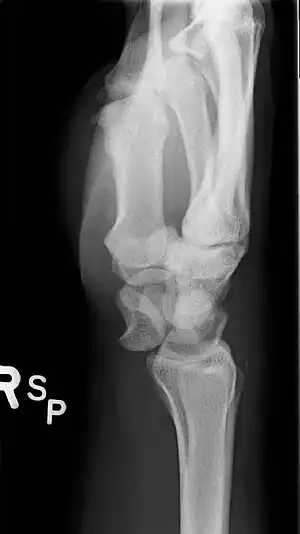

| A lateral X-ray of the wrist showing a lunate dislocation | |